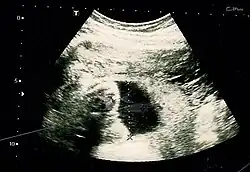

3D ultrasound of 75-millimetre (3.0 in) fetus (about 14 weeks gestational age)

Fetal assessments

Obstetric ultrasonography is routinely used for dating the gestational age of a pregnancy from the size of the fetus, determine the number of fetuses and placentae, evaluate for an ectopic pregnancy and first trimester bleeding, the most accurate dating being in first trimester before the growth of the foetus has been significantly influenced by other factors.[22] Ultrasound is also used for detecting congenital anomalies (or other foetal anomalies) and determining the biophysical profiles (BPP), which are generally easier to detect in the second trimester when the foetal structures are larger and more developed.[23]

X-rays and computerized tomography (CT) are not used, especially in the first trimester, due to the ionizing radiation, which has teratogenic effects on the foetus.[24] No effects of magnetic resonance imaging (MRI) on the foetus have been demonstrated,[25] but this technique is too expensive for routine observation. Instead, obstetric ultrasonography is the imaging method of choice in the first trimester and throughout the pregnancy, because it emits no radiation, is portable, and allows for realtime imaging.[26]

The safety of frequent ultrasound scanning has not been confirmed. Despite this, increasing numbers of women are choosing to have additional scans for no medical purpose, such as gender scans, 3D and 4D scans.[27] A normal gestation would reveal a gestational sac, yolk sac, and fetal pole.[28]

The gestational age can be assessed by evaluating the mean gestational sac diameter (MGD) before week 6, and the crown-rump length after week 6. Multiple gestation is evaluated by the number of placentae and amniotic sacs present.[29]